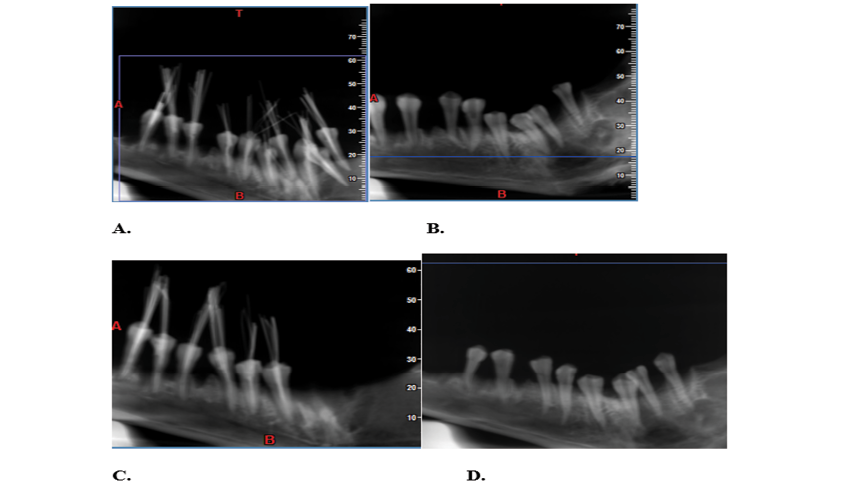

Figure 1. CBCT images of the teeth; (A) presence of broken file + obturation, (B) presence of broken file, no obturation. (C) absence of broken file + obturation, (D) absence of broken file, no obturation